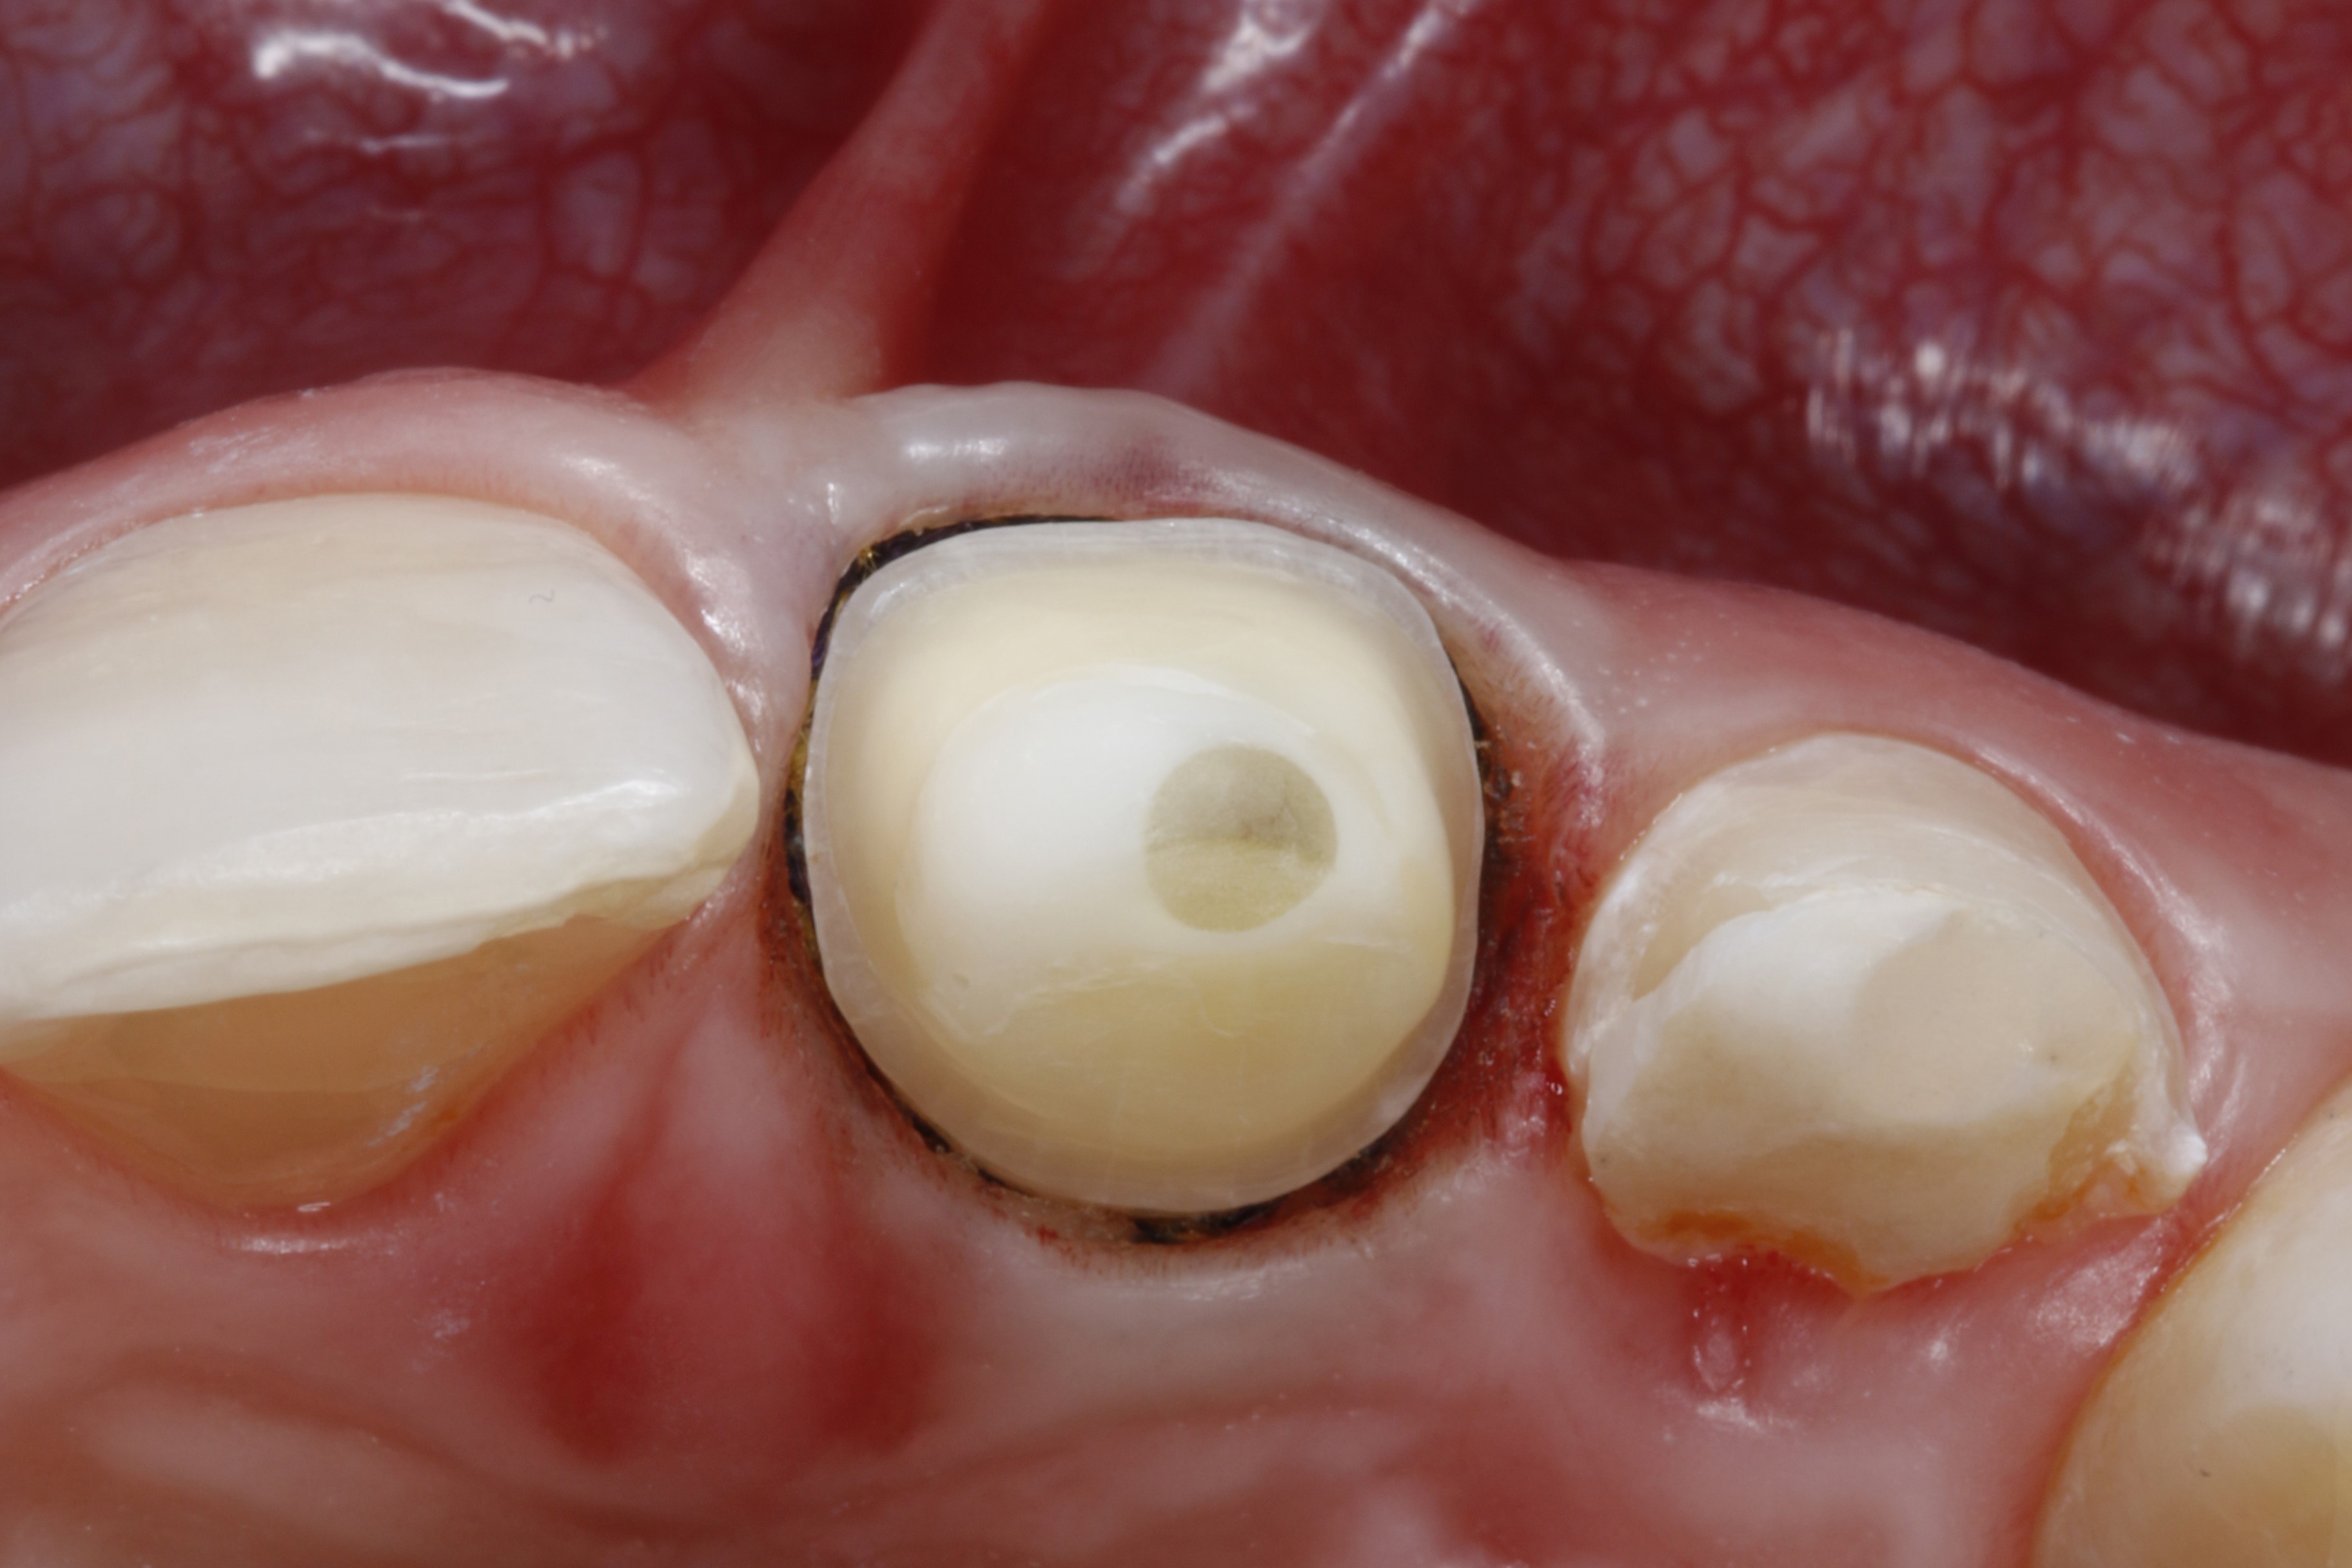

Ryc. 4. Ząb 21 od strony brzegu siecznego – widoczny zacementowany adhezyjnie, wzmocniony włóknem szklanym wkład koronowo‑korzeniowy (Rebilda Post, VOCO).